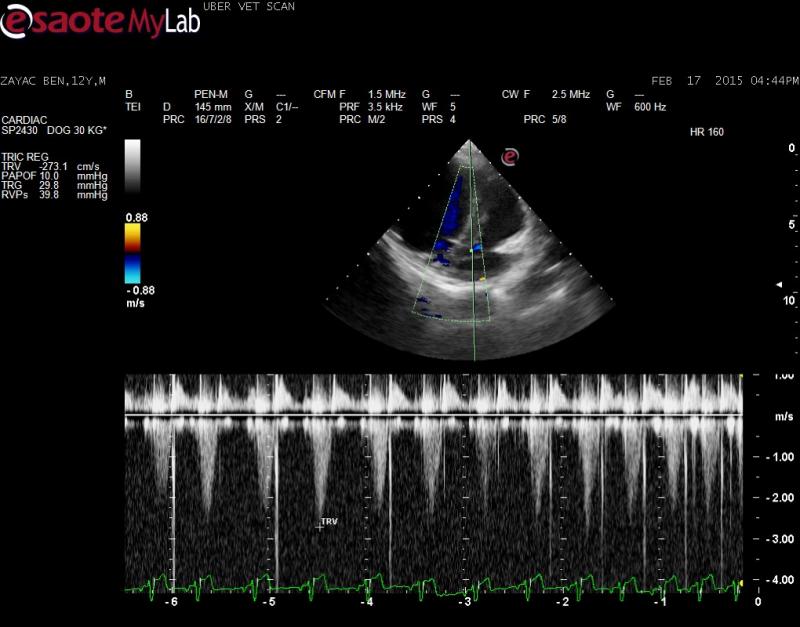

– echo showed normal LA size, no evidence of PAH so to me the cough is likely related to lung disease and this needs to be further worked-up (bronchial airway disease etc); mild MR and TR present

Of course the clip you want, I did not save! I have added two tranverse right parasternal views, if this may help? They are slightly obliqued ๐